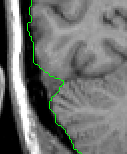

Take care to exclude all dura mater and sinuses.

Moving posteriorly, take care to exclude the Superior Sagittal Sinus, as it is often included by the automation.

In the middle portion of the ICC, continue extracting all Cortex and CSF, but be aware of and exclude all veins, cranial nerve roots, and bony protuberances that appear, particularly as the brainstem appears.